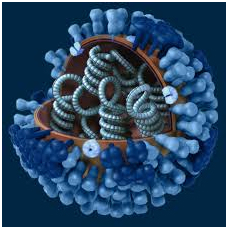

- آنفولانزا: این بیماری عامل 5 تا 3 میلیون مورد بیماری شدید است که 500000 تا 250000 نفر در سال به دلیل ابتلا به این بیماری فصلی دچار مرگ می شوند. به طور دوره ای این بیماری عفونی ویروسی بسیار شیوع پیدا کرده و سلامتی بسیاری از مردم را تهدید می کند. در اوایل سال 1918حدود 50 میلیون نفر از مردم سراسر جهان به این بیماری دچار شدند. برخی از انواع این بیماری مانند آنفولانزای خوکی و آنفولانزای پرندگان می تواند از سایر جانوران نیز به انسان منتقل گردد.